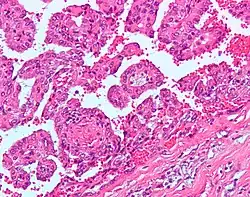

Ранее рак почки классифицировали по типу клеток и характеру роста. Позже было установлено что рак почки в абсолютном большинстве — смешанный. Современная классификация основывается на морфологических, цитогенетических и молекулярных исследованиях, а также иммуногистохимическом анализе и выделяет 5 видов почечно-клеточного рака[35]:

- папиллярный (1 и 2 подтип) рак почки

Папиллярный почечно-клеточный рак при этом включает два отдельных подтипа: 1-й из них представлен мелкими клетками со светлой цитоплазмой, 2-й — крупными клетками и эозинофильной цитоплазмой (для данного подтипа вероятность развития метастазов выше)[17].